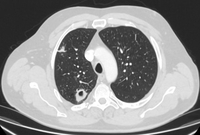

Computed tomography (CT) showing a benign calcified granuloma in the right middle lobe, stable >10 years. The patient reported previous pneumonia on the same side

From the collection of Dr George Tsaknis, MD, PhD, FRCP(London), MRQA, MAcadMEd, PGCert; used with permission